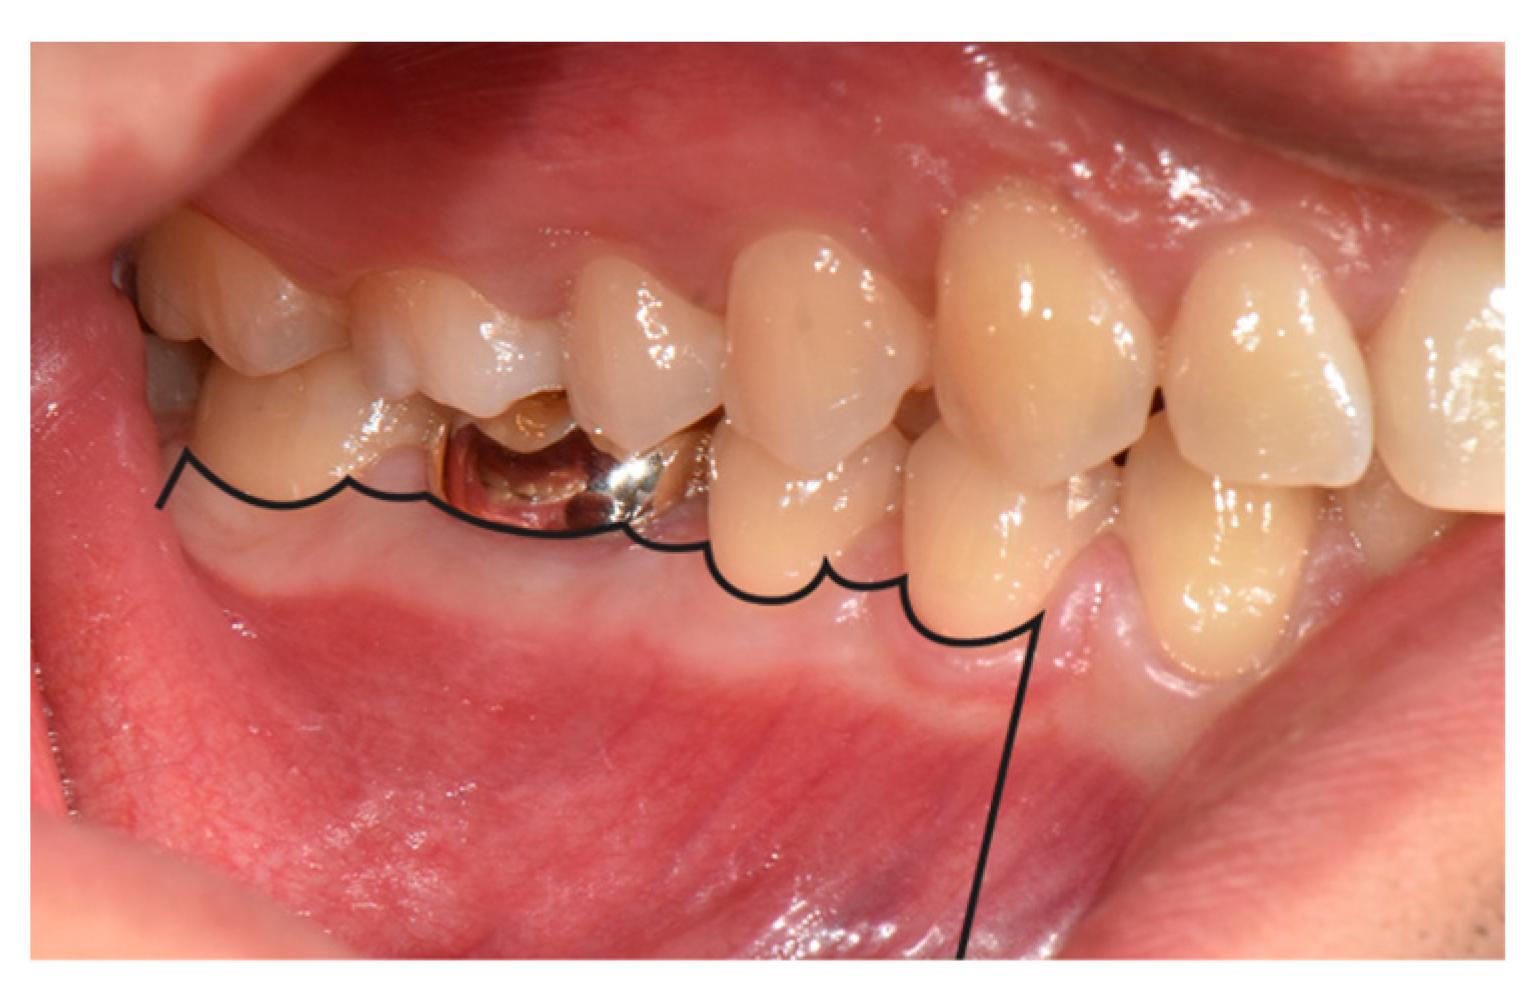

3.1. Flap Design

- Velvart, P. Papilla base incision: A new approach to recession-free healing of the interdental papilla after endodontic surgery. Int. Endod. J. 2002, 35, 453–480. [Google Scholar] [CrossRef] [PubMed]

- Velvart, P.; Ebner-Zimmermann, U.; Ebner, J.P. Comparison of long-term papilla healing following sulcular full thickness flap and papilla base flap in endodontic surgery. Int. Endod. J. 2004, 37, 687–693. [Google Scholar] [CrossRef] [PubMed]

- von Arx, T.; Vinzens-Majaniemi, T.; Bürgin, W.; Jensen, S. Changes of periodontal parameters following apical surgery: A prospective clinical study of three incision techniques. Int. Endod. J. 2007, 40, 959–969. [Google Scholar] [CrossRef] [PubMed]